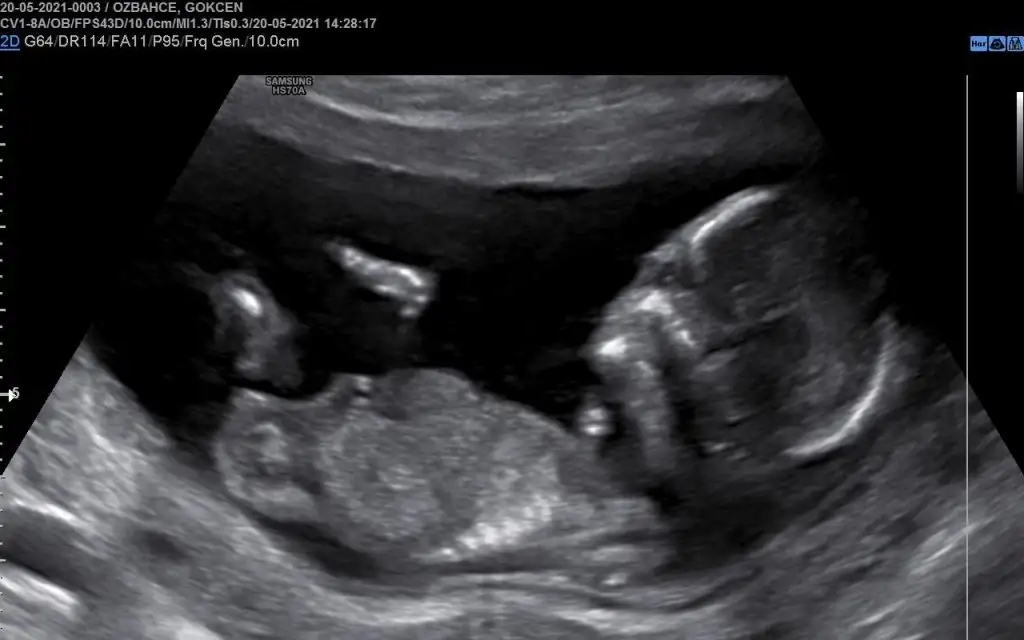

Kızlar iyi pazarlaar :KK54: 14+5'te görüş almak için bir perinatoloğa gitmiştim. Oradaki ultrason görüntüsünü paylaşacağım sizlerle ama doktorun tahminini söylemeyeceğim şimdilik çünkü kesin demedi, hala yanıltıcı olabiliyor dedi. 12+3 te falan da her zamanki gittiğim doktor başka demişti ama çok erken, yanılıyor olabilirim de demişti :)

Bakalım sizler ne diyeceksiniz :)